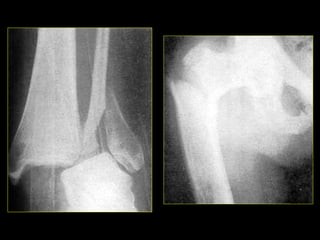

• #10 Fractura de la base del V metatarsiano (izq). Fx desplazada de cúbito y radio (sup-der); Fx desplazada tibia peroné.